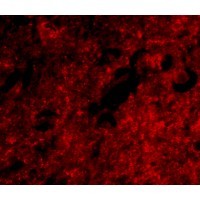

- Experimental details

- Immunofluorescence of slitrk1 in human brain tissue with slitrk1 antibody at 20 ug/mL.

- Validation comment

- IF